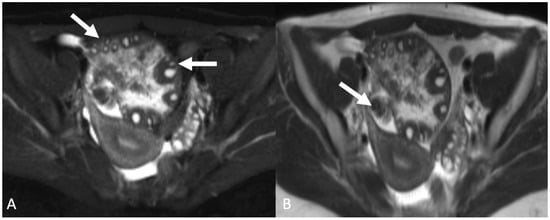

5.2. Uterine Lesions

5.2.1. Uterine Vasculature

5.2.2. Leiomyoma

5.3. Peritoneal Disease